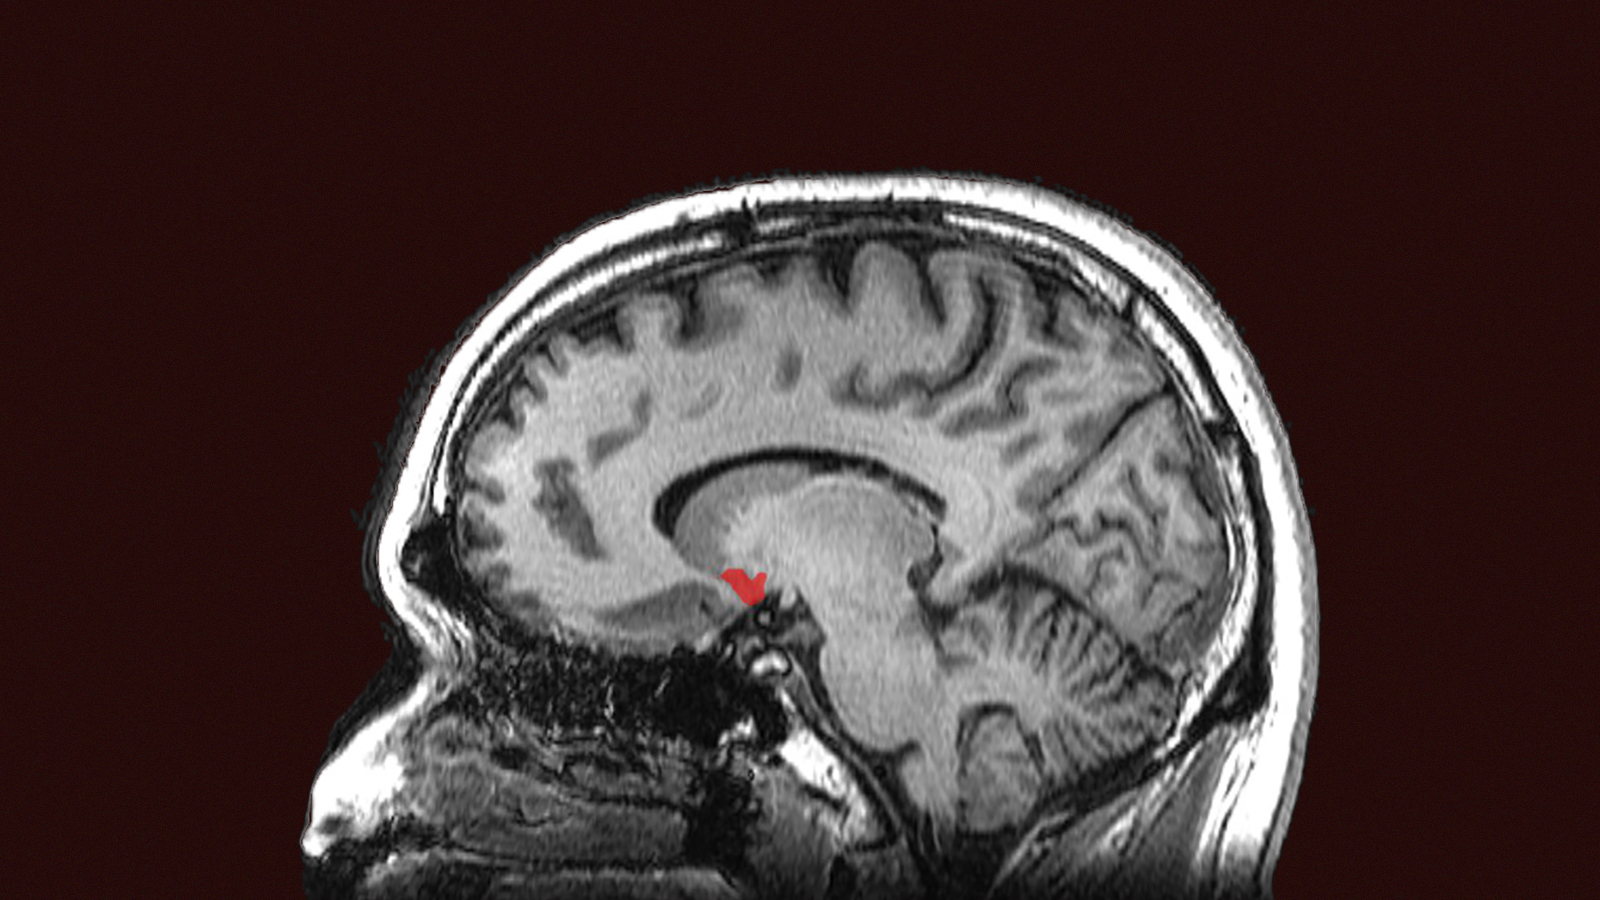

But the exact location of the brainstem respiratory-pattern generator remained unknown until the late 1980s, when Feldman and colleagues narrowed it down to a network of about 3,000 neurons in the rodent brainstem (in humans it contains about 10,000 neurons). It’s now called the preBötzinger Complex (preBötC). Neurons there spontaneously exhibit rhythmic bursts of electrical activity that, relayed through intermediate neurons, direct the muscles that control breathing.